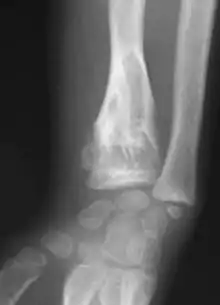

X-ray showing enchondromas localized in the lower part of the radius of a 37-year-old patient affected with Ollier disease